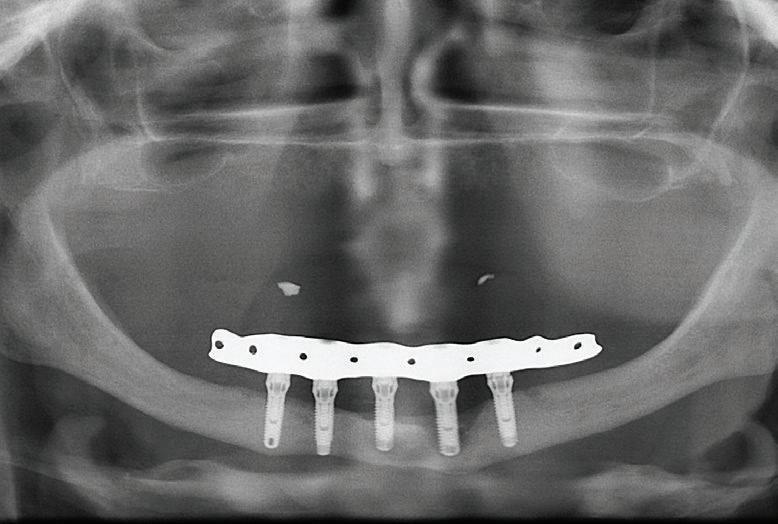

Ce module a pour objectif de vous permettre de diagnostiquer, planifier et réaliser des restaurations complètes fixes et amovibles sur implants, que ce soit sur barre ou à l’aide d’attaches individuelles. Il s’adresse aux professionnels souhaitant approfondir leur compréhension des options de traitement en édentation complète, partielle ou en dentition terminale.

Vous apprendrez à distinguer les différents profils cliniques, à reconnaître les indications et limites des diverses restaurations (mandibule et maxillaire), et à orienter vos patients vers des solutions adaptées à leurs besoins et attentes.

Tout au long de la formation, vous profiterez de l’expertise développée au Centre à travers plus de 3 500 cas d’édentation complète traités et aurez l’occasion d’observer en direct les étapes chirurgicales et prothétiques, que ce soit en salle ou via une retransmission depuis la salle de cours.

Principes biomécaniques :

Nombre et position des implants selon le type de restauration (fixe/amovible, barre/attaches)

Considérations biomécaniques en édentation complète

Étapes chirurgicales :

Survol des étapes chirurgicales liées aux différents types de restaurations